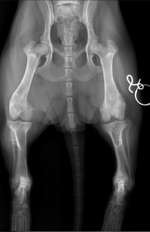

Hallo, meine dreijährige Hündin ist eigentlich immer früh wach und kann es kaum erwarten zu fressen. Seit einer Woche bleibt sie liegen und schläft, sie frisst morgens nichts. Ansonsten ist sie normal, sie spielt und kuschelt, der Kot ist normal. Abends frisst sie dann, wenn ich daneben stehen bleib ...